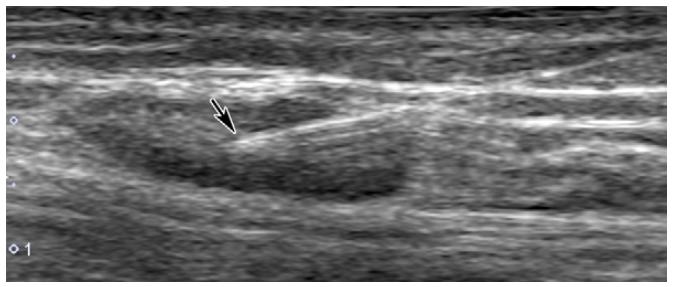

复发/难治性盆腔淋巴囊肿可尝试应用淋巴管栓塞术。在超声引导下,应用微穿针穿刺,微穿针远端置于淋巴结皮质与髓质之间,经微穿针缓慢注入超液化碘油,DSA密切监测淋巴管显影情况,必要时术中CBCT监测淋巴管显影。

超声引导下穿刺淋巴结